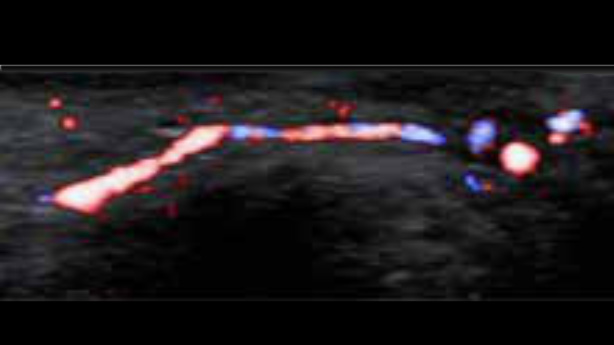

EcĂłgrafo Zeus presenta una interfaz fĂĄcil de usar y funciones sencillas para realizar exploraciones eficientes. Sus versĂĄtiles capacidades abarcan la ecografĂa abdominal, vascular, de partes peque?as y musculoesquelĂ©tica, lo que aumenta la confianza en el diagnĂłstico.